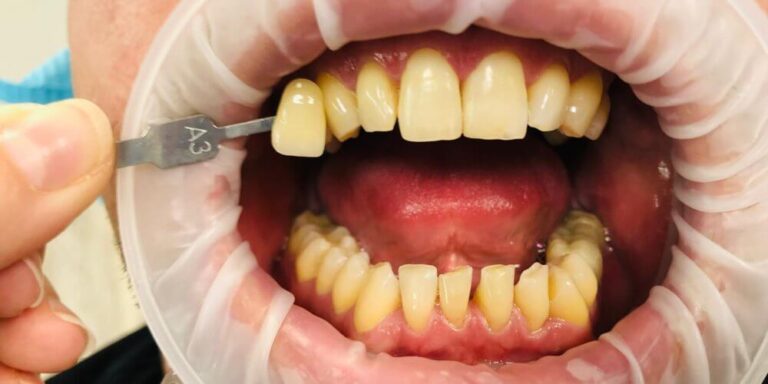

Profilaktyka jest kluczem do uzyskania i utrzymania pożądanego efektu wybielania zębów. Niezwykle istotnymi jej elementami są zabiegi polegające na oczyszczaniu zębów z osadów i kamienia.

Pozwalają one utrzymać dziąsła i kość w dobrej kondycji, a co za tym idzie – również zęby. W naszym gabinecie kamień nazębny czyścimy skalerem ultradźwiękowym, osad natomiast piaskiem przy użyciu piaskarki Prophy Jet wykorzystującej w swej pracy ciśnienie wodne.

Ten sposób wybielania zębów w gabinecie stomatologicznym jest najbezpieczniejszy i przynosi najszybsze efekty. Podczas zabiegu nakładamy na zęby specjalny żel wybielający, a następnie aktywujemy go za pomocą światła lampy Beyond.

Metoda ta pozwala rozjaśnić zęby nawet o 14 tonów. Sekretem jej skuteczności jest receptura nakładanego na zęby żelu, którego składniki aktywują odpowiedniej długości i mocy fale świetlne emitowane przez lampę.

Ta metoda wybielania zębów skuteczna jest nawet w przypadku Pacjentów, którzy od urodzenia posiadają ciemniejszy odcień zębów oraz tych, którzy nabawili się poważnych przebarwień szkliwa.